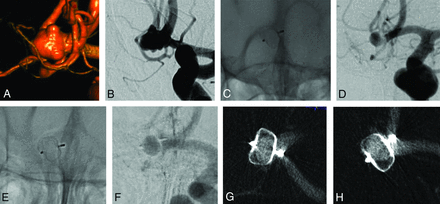

All aneurysms and patients underwent at least 1 VasoCT during the follow-up, showing partial WEB opacification without neck or aneurysm opacification (Fig 2) in 3 patients (patients 2, 5, and 6), complete WEB opacification without neck or aneurysm opacification (Fig 3) in 3 patients (patients 1, 7, and 8), partial WEB opacification and neck opacification (Fig 4) in 1 patient (patient 3), and complete WEB opacification and dome opacification (Fig 5) in 1 patient (patient 4). This last patient was treated with an inappropriately oversized (mean aneurysm width, 6.7 mm, and the implanted device was a WEB 17 SL 7 × 3 mm) WEB device.

3D (A) and 2D (B) DSA show an anterior communicating artery aneurysm. Nonsubtraction (C) and subtraction (D) images of the first DSA follow-up after 6 months and of the latest DSA follow-up after 4 years (E and F) show complete filling of the WEB with contrast. VasoCT in 2 different views (G and H) shows opacification of the WEB and no opacification of the aneurysm.